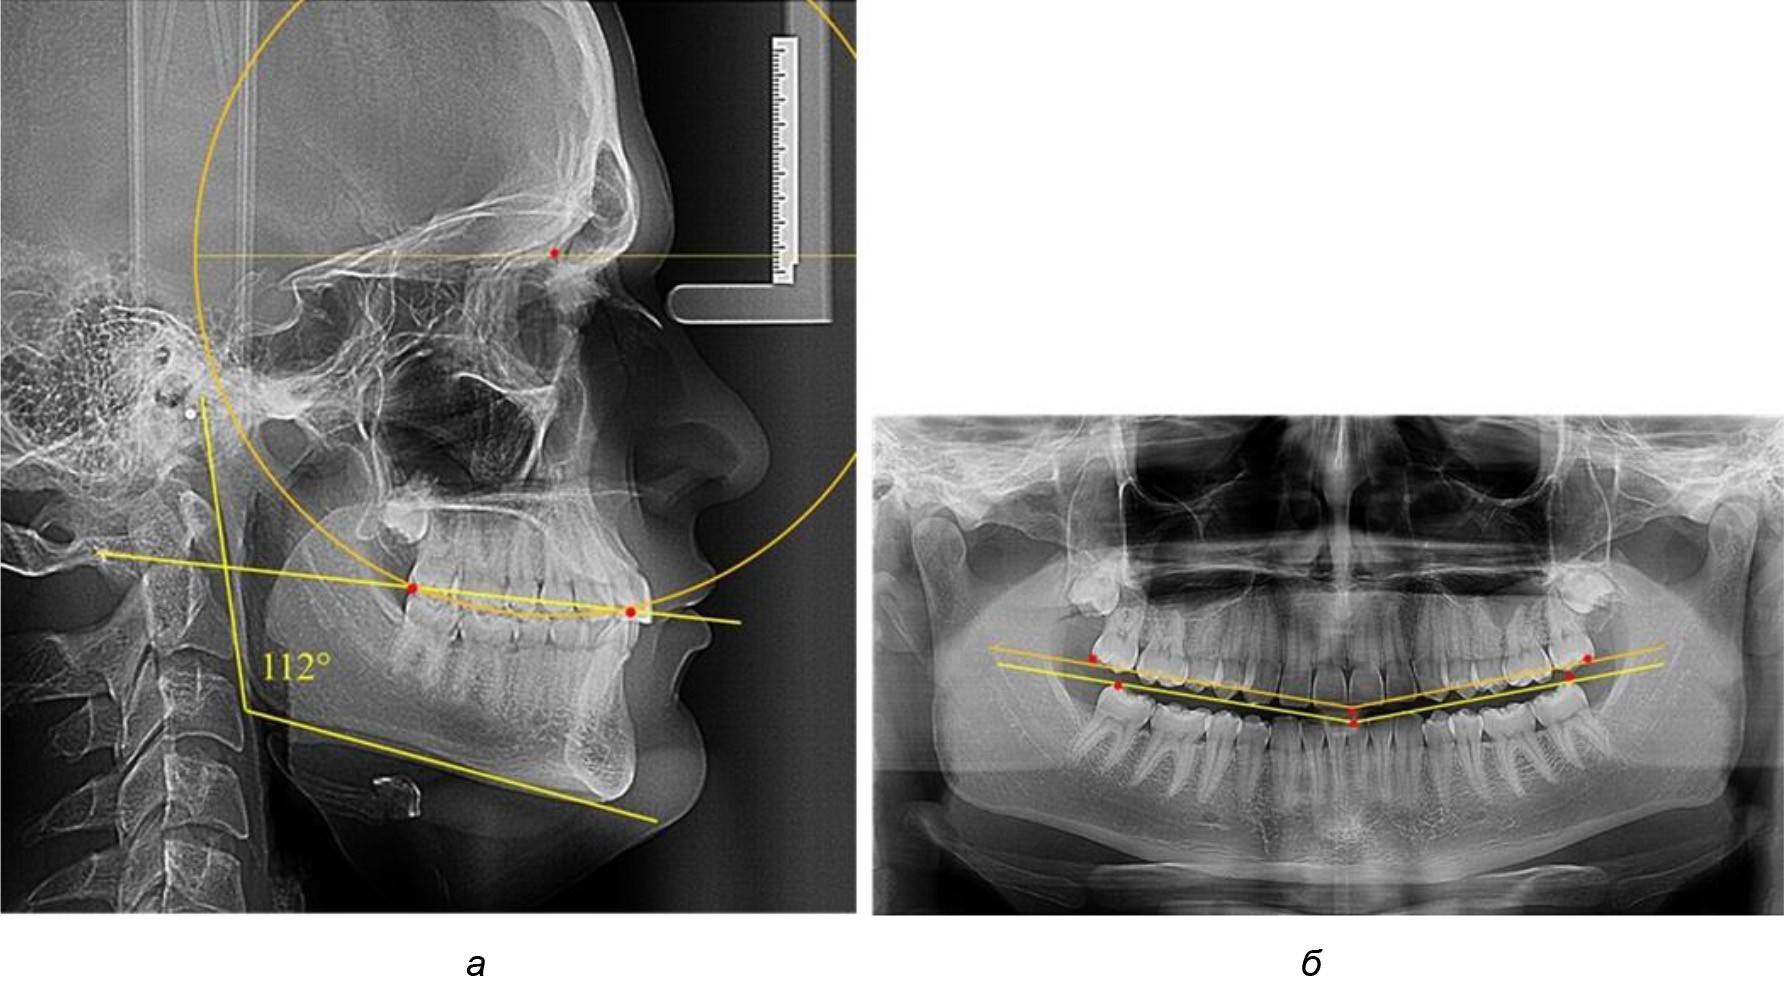

Рис. 4. Особенности кривой Spee на ТРГ (а) и ОПТГ (б) у людей с горизонтальным типом лица

В 3-ю подгруппу вошли ТРГ и ОПТГ 14 человек 1-й группы, что составило (22,58 ± 5,31) % от общего количества людей 1-й группы. Величина угла нижней челюсти в среднем составила (114,85 ± 2,87)° и характеризовала горизонтальный тип нижней челюсти.

Глубина кривой Spee в среднем по 2-й подгруппе составил (2,94 ± 0,47) мм, что было меньше, чем в других подгруппах. Деление величины радиуса круга к длине окклюзионной линии составило 1,616 ± 0,02 (рис. 4).